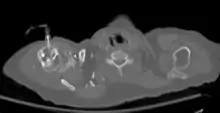

The needle is inserted through the bone's hard cortex and into the soft marrow interior, which allows immediate access to the vascular system. The IO needle is positioned at a 90 degree angle to the injection site, and is advanced through manual traction, impact driven force, or power driven. Each IO device has different designated insertion locations. The most common site of insertion is the antero-medial aspect of the upper, proximal tibia as this site lies just under the skin and is easily located. Other insertion sites include the anterior aspect of the femur, the superior iliac crest, proximal humerus, proximal tibia, distal tibia and the sternum (manubrium).[1] Although intravascular access is still the preferred method for medication delivery in the prehospital area, IO access for adults has become more common. As of 2010, the American Heart Association no longer recommends using the endotracheal tube (ET )for resuscitation drugs, except as a last resort when IV or IO access cannot be gained.[1] ET absorption of medications is poor, and optimal ET drug dosings are unknown. IO administration is becoming more common in civilian and military pre-hospital emergency medical services (EMS) systems globally.[11]